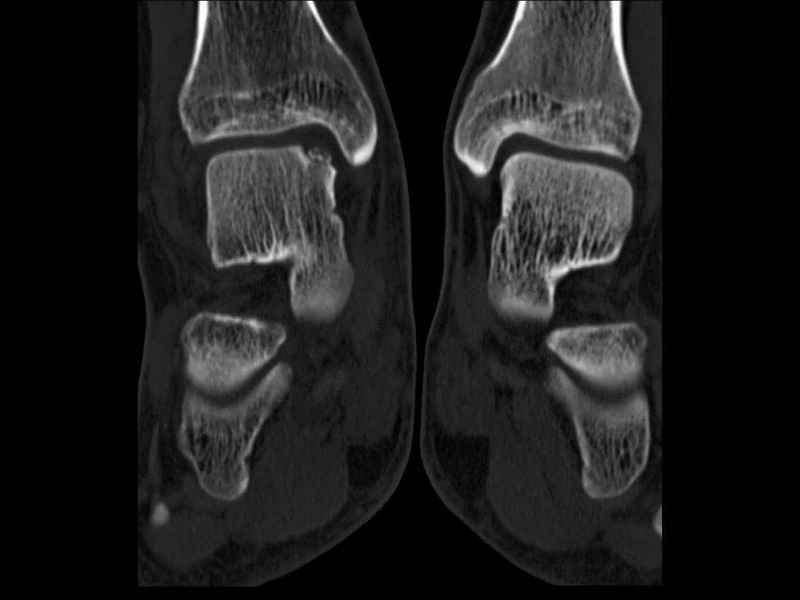

Уважаемые коллеги, обратился за помощью пациент, мужчина, 25 лет. С жалобами на болевой синдром в области голеностопного сустава и среднем отделе стопы. Травму отрицает. Со слов, болевой синдром в течении 1 года. Последние 1-1.5 мес периодически вынужден пользоваться костылями. После ограничения нагрузки боли уменьшаются.Соматически здоров. До появления болей активно занимался рукопашным боем. На СКТ картина рассекающего остеохондрита блока таранной кости, киста шейки таранной кости с признаками импрессии суставной поверхности. А также - разрастания переднего края б\берцовой кости сопровождающиеся клиникой импиджмент синдрома. Предполагаемый план лечения- удаление свободного фрагмента суставного хряща из трансмаллеолярного доступа с рассверливанием поверхности дефекта, кюретаж кисты шейки с заполнением полости биокомпозитом + дебридмент переднего отдела голеностопного сустава. Прошу высказать своё мнение, за и против, предполагаемого плана лечения. А также по возможности ответить на вопросы: 1. Есть ли необходимость в улучшении васкуляризации таранной кости (например подтаранный артродез). 2. Учитывая планируемое применение биокомпозитного цемента целесообразно ли заполнение им дефекта блока таранной кости с моделированием края суставной поверхности.

СТ чётко демонстрирует секвестр, но открыв сустав вероятно, что хрящ тарана окажется интактным и только пальпацией/ ЭОП можно будет

идентифицировать локализацию секвестра. Если вы с этим столкнетесь, то секвестрэктомию я бы предложил сделать не со стороны суставной поверхности тарана, а со стороны угла тарана, субхондрально кюрретаж стенок, разнонаправленную туннелизацию спицей или 1.1мм сверлом и заполнить дефект спонгиозным графтом.